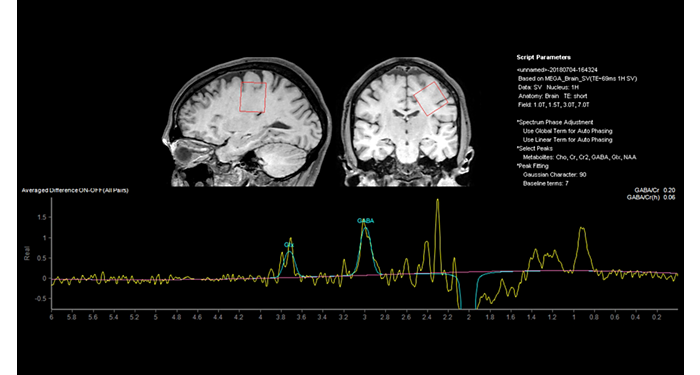

70% of radiologists consider neuro indications to be challenging, mostly due to a lack of appropriate imaging and visualization techniques¹. Philips aims to provide the best possible diagnostic clarity and treatment guidance for all patients with neurological disorders. By leveraging our dStream digital platform, this year, we are introducing, a set of novel imaging and visualization strategies. These may empower you to resolve complex neuro questions with more certainty, as well as unlock new neuro territories in advanced Neurofunctional applications. This is a key step towards elevating neuro diagnostics and ultimately touching more lives with MR imaging. ¹ TMTG Market Survey 2016

New neuro applications